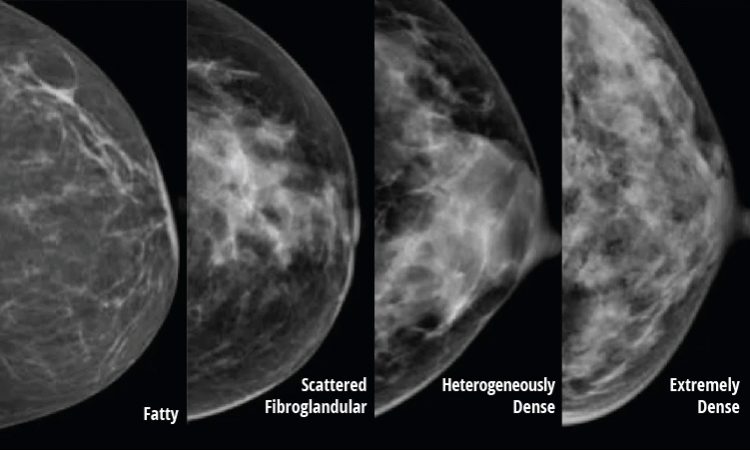

It is a misconception that if a woman’s breasts feel firm, they must be dense. The only way to tell if you have dense breasts is with a mammogram. After examining the image, your radiologist will fit you into one of four categories, according to your breast density.

- Mostly Fatty Tissue

- Scattered Fibroglandular Tissue

- Heterogeneously Dense

- Extremely Dense

The Breast Imaging Reporting and Data System (BI-RADS) is a standardized classification system that radiologists use to report breast density findings. They grade breast density on a scale of 1 to 4. Here is what those grades mean:

- BI-RADS 1: Breast tissue is almost entirely fat, with less than 25% of the breast composed of glandular tissue.

- BI-RADS 2: Breast tissue contains scattered fibroglandular densities, with between 25% and 50% of the breast composed of glandular tissue.

- BI-RADS 3: Breast tissue is heterogeneously dense, with between 51% and 75% of the breast composed of glandular tissue.

- BI-RADS 4: Breast tissue is extremely dense, with more than 75% of the breast composed of glandular tissue.

Dense breast tissue also makes it difficult to detect cancer using traditional mammography alone. On a mammogram, dense breast tissue appears white – but so do breast masses and cancers. In contrast, cancers are easier to detect in non-dense breasts because fatty tissue appears black on a mammogram, so the white cancer stands out like a lightbulb against a black background.